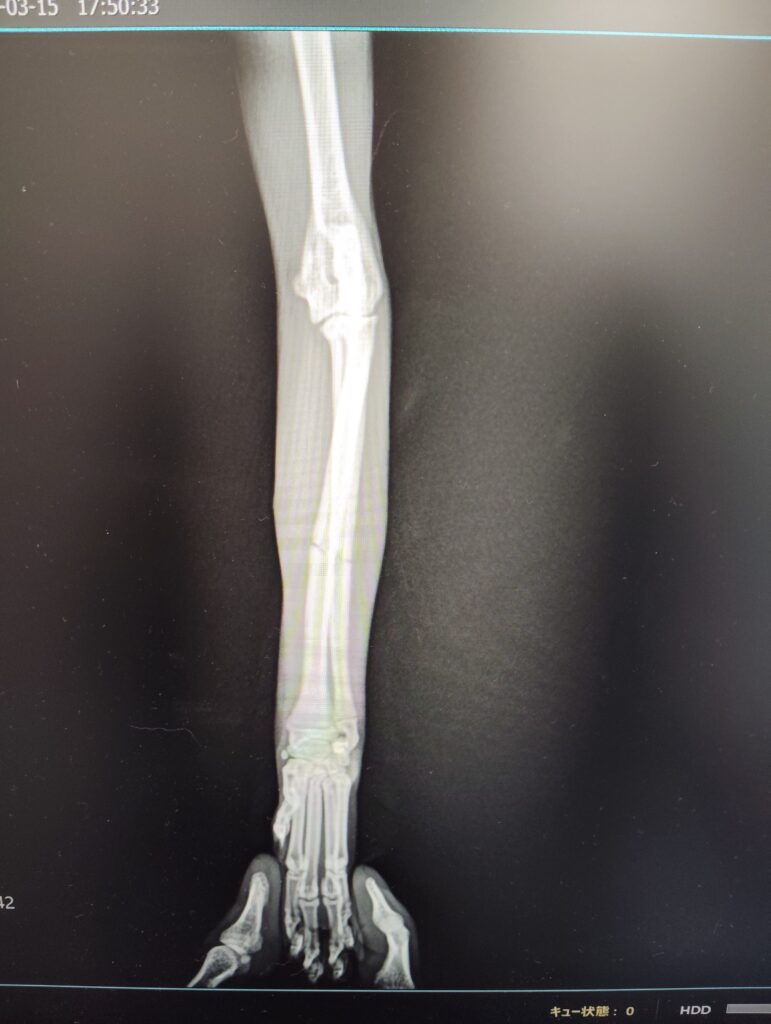

猫の橈尺骨骨折

日本猫、避妊メス、1歳

高所から落下後、前足を挙上

【レントゲン検査】

・左橈尺骨横骨折